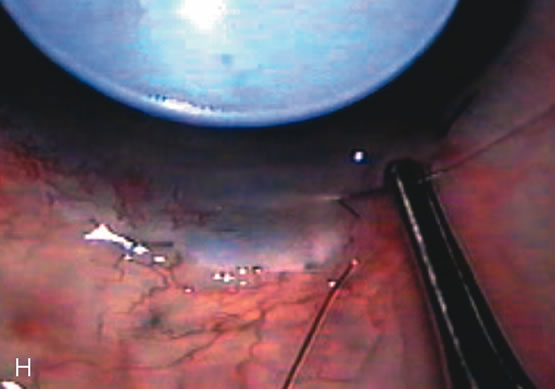

In years past, patients with both cataract and glaucoma frequently provided overwhelming surgical challenges for the ophthalmologist. The ability to carry out phacoemulsification through a 3.2-mm corneal incision along with inserting a foldable IOL is a vast improvement over 11-mm incisions that were common a decade ago (Fig. 1). The anatomical and inflammatory changes to the eye are less with small incision techniques, improving the likelihood of success with concomitant glaucoma surgery. Pharmacologic inhibition of fibrosis along with postoperative wound revision increases the long-term success rate of filtration surgery when combined with lens extraction. (Fig. 2). The learning curve may be steep at times, but the blending of cataract and glaucoma surgical skills slowly falls into place as the surgeon constantly learns and upgrades his or her technique.

Fig. 2. Wound modulation and revision. A. MMC decreases the likelihood of bleb failure in high-risk eyes undergoing combined cataract and glaucoma surgery. Overusage of this potent cytotoxic drug should be avoided owing to a myriad of problems related to the formation of an avascular bleb. B. Office-based laser revision of the operative wound allows for increased postoperative flexibility with less complications. The correct number and tension of scleral flap sutures allows the surgeon to strive for a safe immediate postoperative IOP range. When fibrosis occurs at approximately 1 week, suturelysis or release of sutures increases filtration while avoiding unwanted hypotony.